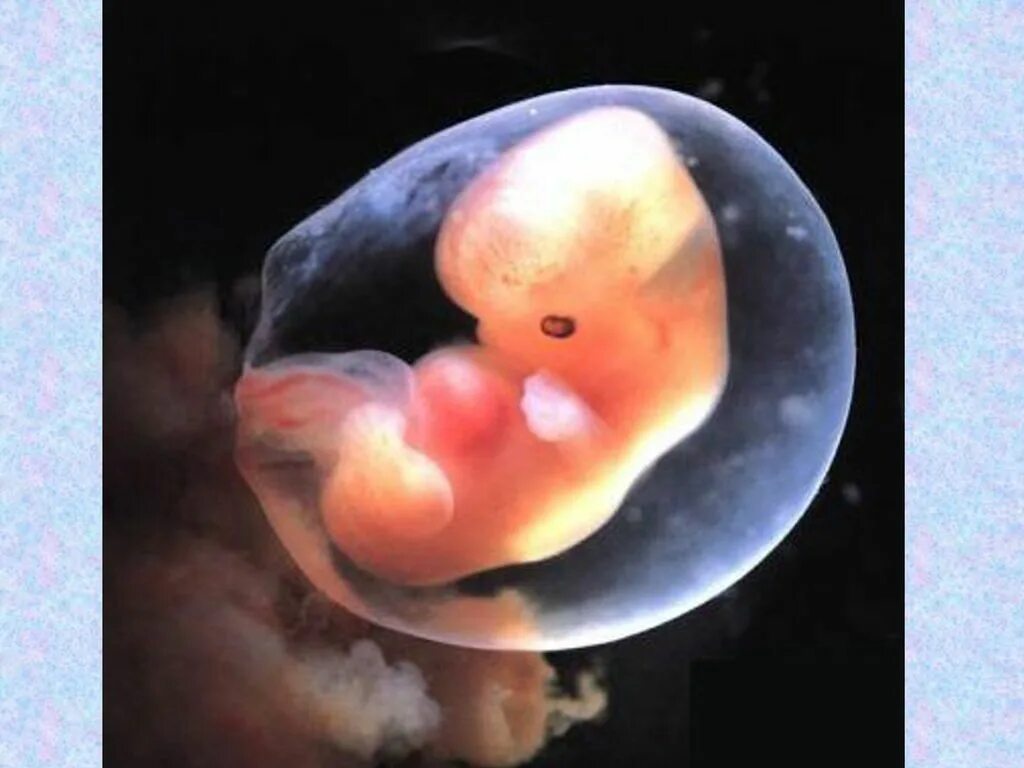

10 week old